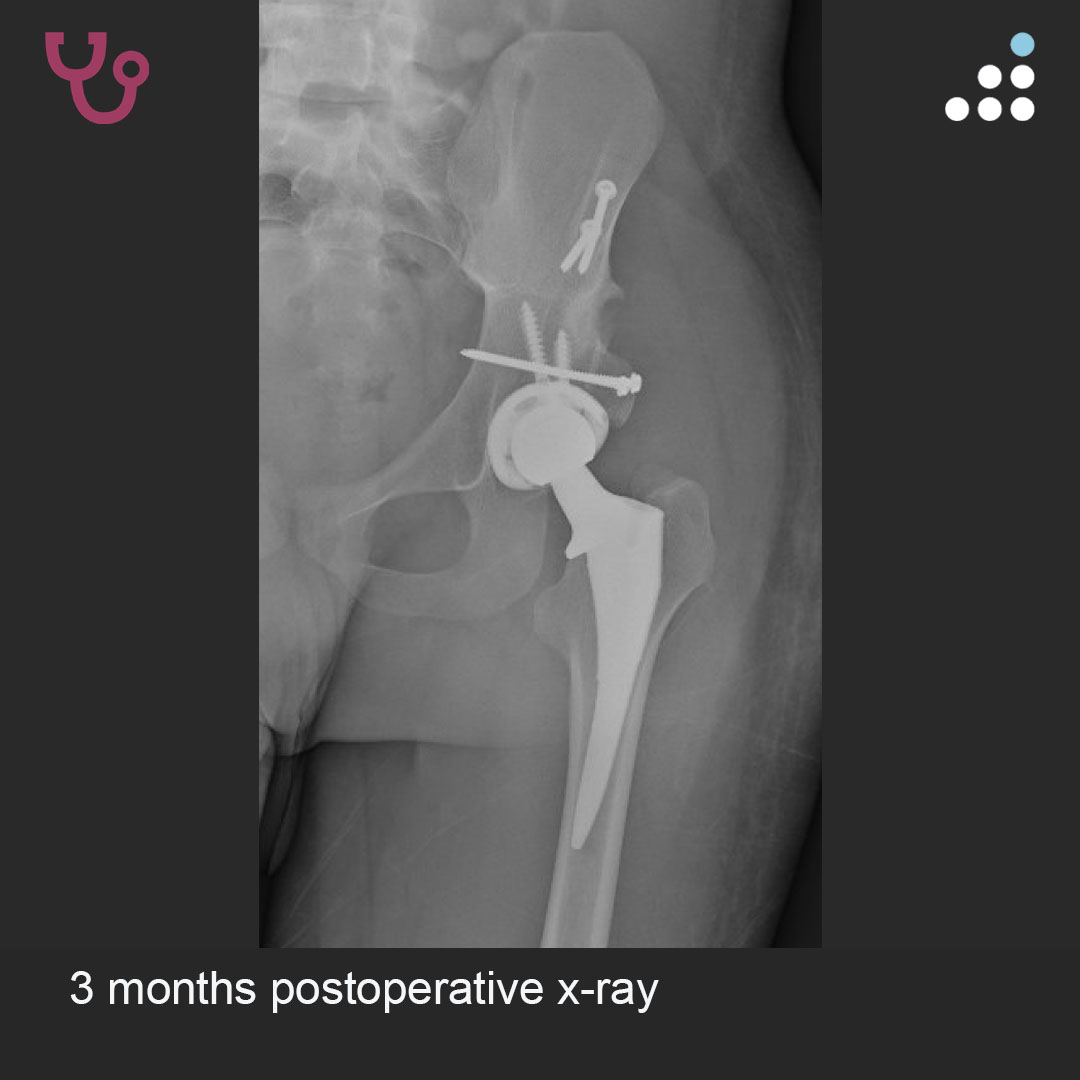

Here are intraop & postop images of yesterday's case by Dr. Jesse Otero (@jesseoteromdphd) and @OrthoCarolina.

DYSPLASTIC HIP IN 20M WITH CEREBRAL PALSY

PROCEDURE:

1. Percutaneous adductor tenotomy.

2. Acetabular augmentation with femoral head autograft.

3. Direct Anterior THA.